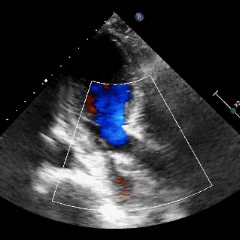

术前超声

超声提示:主动脉瓣右冠瓣脱垂,主动脉瓣中-重度关闭不全,左心系统扩大,二尖瓣少量反流。

术后超声可见反流消失,血流动力学正常